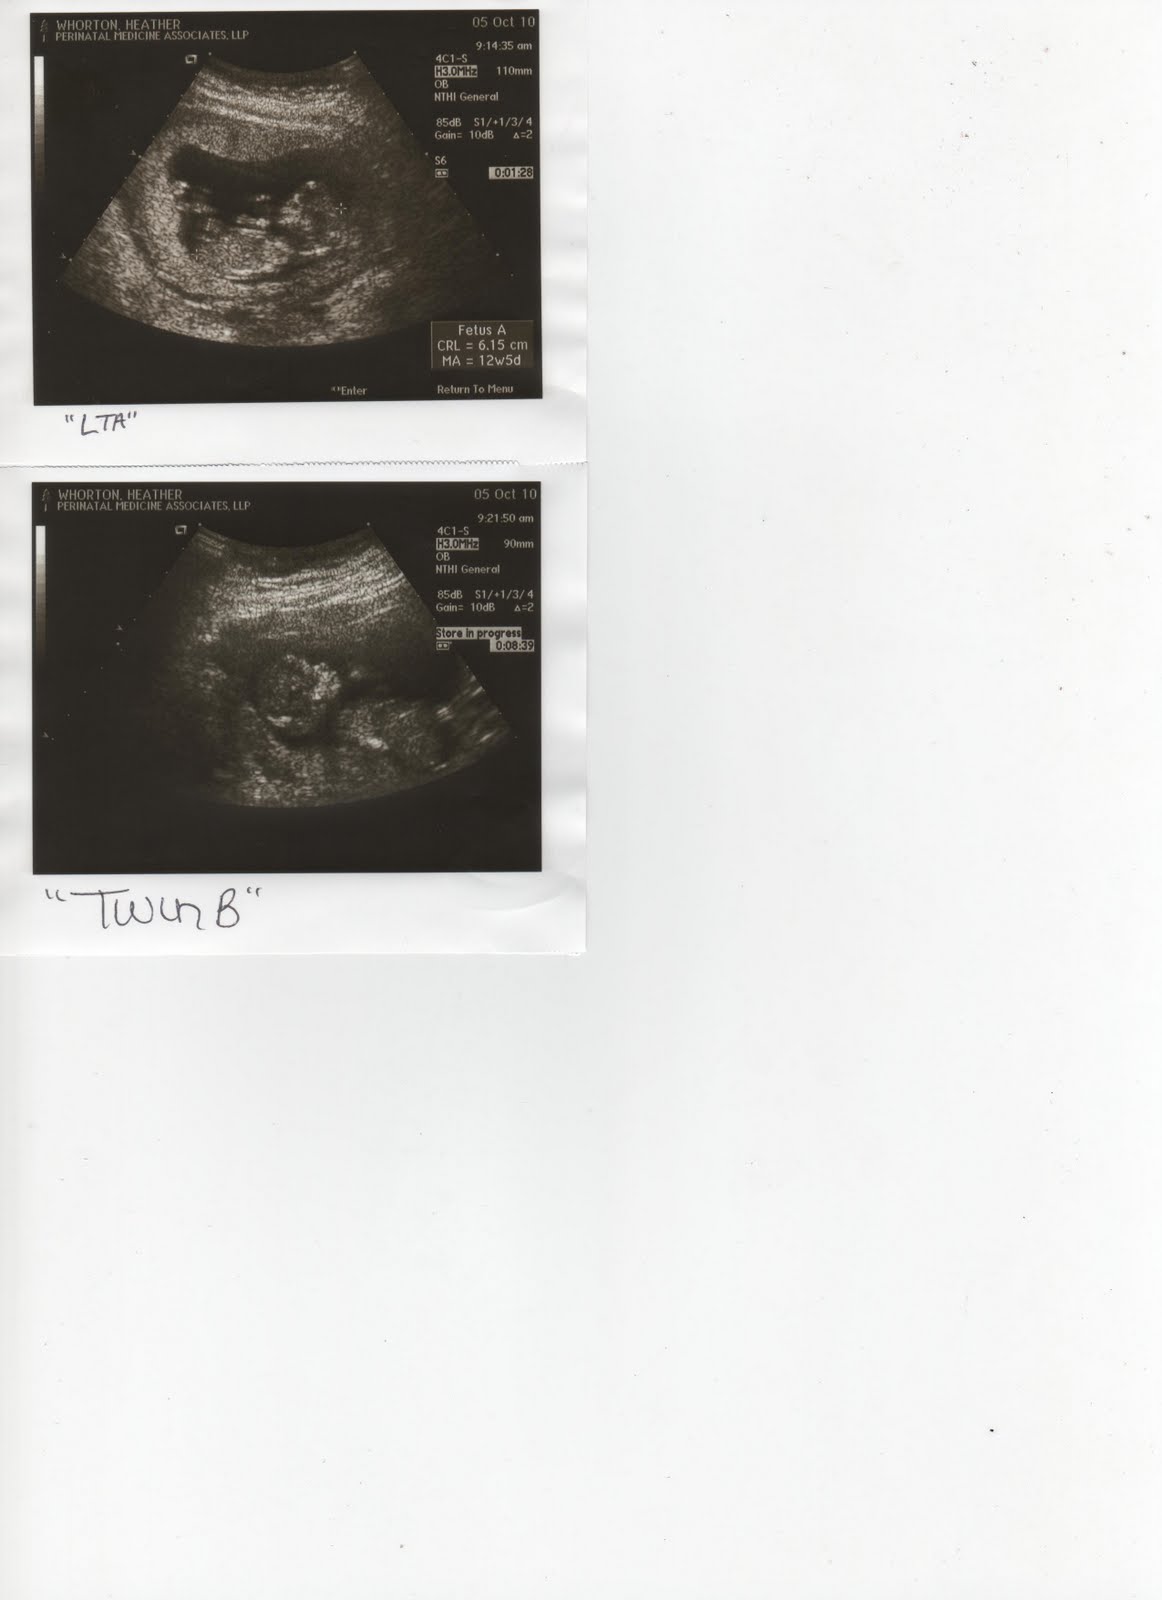

PICTURES!! FINALLY! :)

So, by the look of these pictures, you can tell I'm not as high-tech as I would like to be. I'll figure out a way to enlarge them, so you can have a better view. Notice how BIG my sweet babies are getting!! I will go to obgyn tomorrow, so more pictures to come soon! :)

2 weeks ago, I went for my first sonogram. Dr. McNabb (thank you, Christina, for introducing me to a great doctor!) had a peculiar look on his face, and so did the nurse. This made me VERY nervous, so I said, "What!?! Just tell me!" So, he said, "Well... there's one sack... and there's ANOTHER!" He couldn't actually see 2 babies at that point, so at the time, we just assumed it was one healthy baby, and PERHAPS a baby (or something else).

I just went back on Tuesday, and sure enough, it's TWINS!! I think Chris & I are still in shock, and honestly, I think we'll be in shock until the babies turn 21... This is such a miracle, and I just can't believe what God has in store for us! Chris is going to be a wonderful father, just as he is already a fabulous husband. I just can't wait to see what life will hand us--HOPEFULLY, it will be two healthy and happy babies.